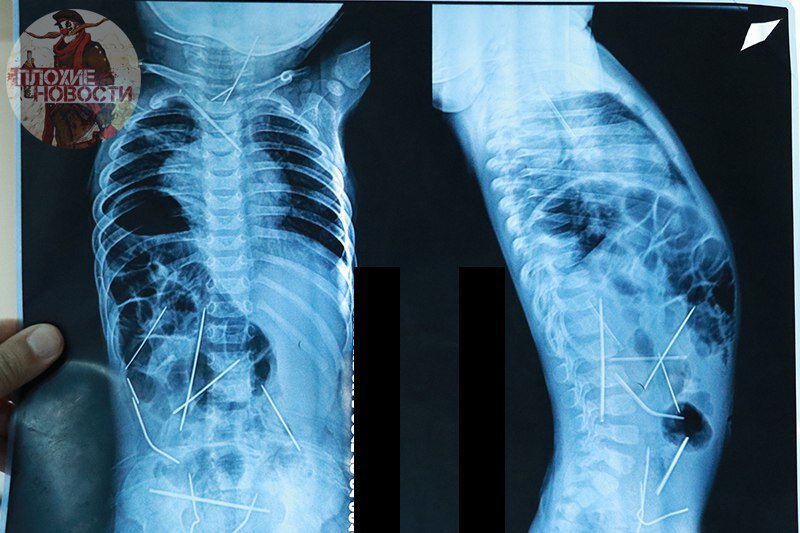

В Ферганской области внутри тела 11-месячного младенца обнаружили 16 иголок

Мать ребенка обратилась к детскому урологу после того, как у него возникли проблемы с мочеиспусканием. Во время осмотра, врач рекомендовал сделать рентген. Во время рентгена было обнаружено, что в теле малыша имеются инородные металлические иглы.

Как сообщает профессор Акилов Хабибулла Атауллаевич, ребенок не мог сам проглотить 16 иголок. Так как рентген показал, что иглы находились в разных местах тела. Тем самым, можно сделать вывод, что иглы были вставлены посторонним человеком.

Стоит отметить, что операция по извлечению игл проходила на протяжении 9 часов. На данный момент ребенок находится в отделении реанимации в крайне тяжелом состоянии.